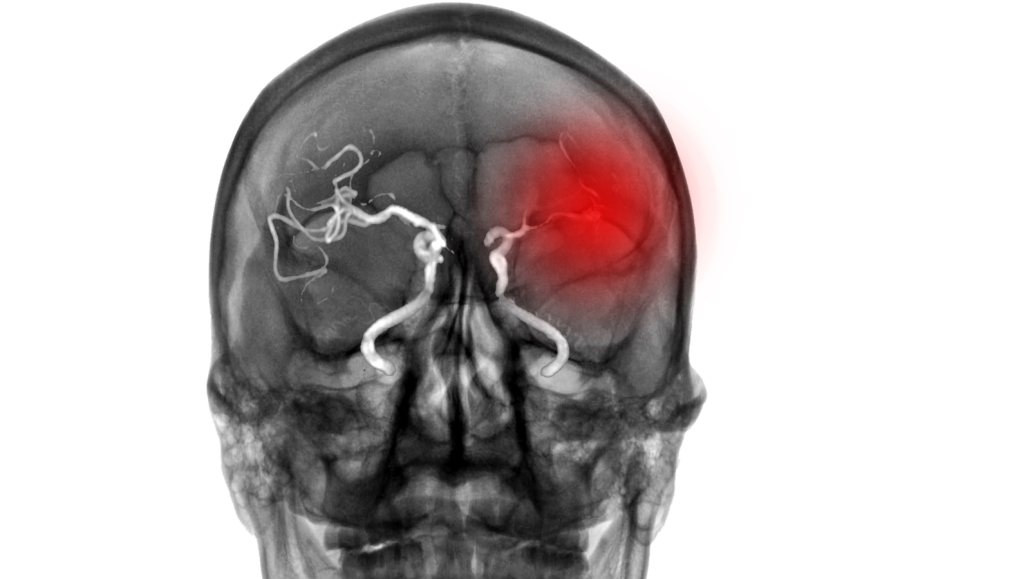

Atherosclerotic stenosis accounts for a high proportion of ischemic stroke and can challenge us as treating physicians. Strokes caused by intracranial stenosis have a high risk of recurrence, so we might be tempted to treat those patients with percutaneous transluminal angioplasty and stenting (PTAS). Of course, every patient with intracranial atherosclerotic stenosis receives best medical treatment (BMT) – consisting of (dual) antiplatelet therapy, blood pressure management and lipid-lowering therapy1. But should patients with symptomatic intracranial stenosis also be treated with stenting or not?

The recently published CASSISS Trial4 enrolled a total of 380 patients and randomized them 1:1 either into the best medical treatment arm versus best medical treatment combined with stenting. Recruited were patients with TIA or nondisabling ischemic stroke (modified Rankin Scale score, 0-2) and severe stenosis (degree of stenosis: 70%-99%) of a major intracranial artery supplying the territory of the ischemic event. The primary outcome, risk of stroke or death within 30 days or stroke in the respective vascular territory within one year, was not significantly different (stenting 8.0% vs medical 7.2%; HR, 1.10 [95% CI, 0.52-2.35]; P = 0.82). In addition, the investigators did not observe a significant difference in the risk of recurrent stroke or death within three years. Why is that? The authors of the trial discuss that periprocedural complications caused by guidewire perforation of arteries and disturbances of vulnerable, atherosclerotic plaque may lead to the lack of superiority of stenting. It goes without saying that this technically challenging procedure requires a high level of experience.